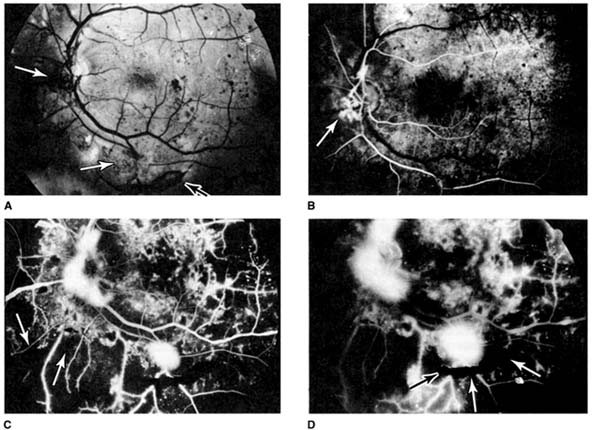

Indirect ophthalmoscopy is so called because one is viewing an "image" of the retina formed by a hand-held "condensing lens." In contrast, direct ophthalmoscopy allows one to focus on the retina itself. Compared with the direct ophthalmoscope (15× magnification), indirect ophthalmoscopy provides a much wider field of view (Figure 2-17) with less overall magnification (approximately 3.5× using a standard 20-diopter hand-held condensing lens). Thus, it presents a wide panoramic fundus view from which specific areas can be selectively studied under higher magnification using either the direct ophthalmoscope or the slitlamp with special auxiliary lenses.

Figure 2-17

Figure 2-17: Comparison of view within the same fundus using the indirect ophthalmoscope (A) and the direct ophthalmoscope (B). The field of view with the latter is approximately 10 degrees, compared with approximately 37 degrees using the indirect ophthalmoscope. In this patient with diabetic retinopathy, an important overview is first seen with the indirect ophthalmoscope. The direct ophthalmoscope can then provide magnified details of a specific area. (Photos by M Narahara.)